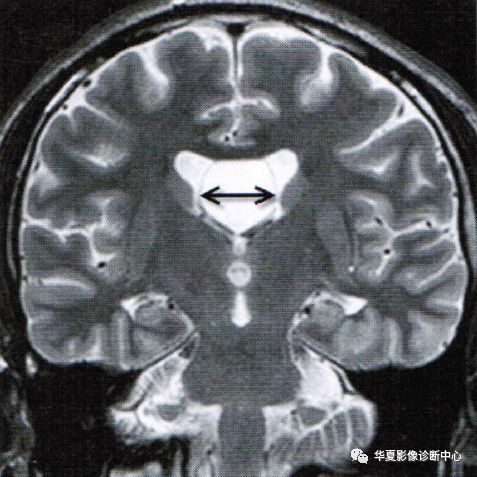

透明隔间腔和Vergae腔

透明隔间腔又称第五脑室,Vergae腔又称穹隆腔或第六脑室;多见于婴幼儿的影像检查,随着年龄增长这些腔隙多数将逐渐闭合,少数永存于成年人。胎儿在4个月时原始透明隔内形成一个中缝,逐渐发展为分离的两个小叶,两叶之间为充满脑脊液的腔隙,即透明隔间腔。vergae腔可与侧脑室或三脑室相通,如果不相通,腔内脑脊液就需要通过透明隔膜过滤,并由隔膜静脉及毛细血管重吸收。成年人的透明隔间腔多数是由先天性因素引起的透明隔发育不全所致,也有报道后天因素可致透明隔间腔或囊肿形成,如外伤导致透明隔撕裂,脑脊液进入两层隔膜之间,形成积液,或外伤后透明隔本身分泌液体充盈已闭合的透明隔间隙,形成囊肿。

Vergae腔位于胼胝体和后穹隆之间,上部和后部是胼胝体的体部与压部,前方和侧方是穹隆柱和体部,下方是穹隆联合,向后下延伸终止于穹隆脚附近。一般认为Vergae腔多为透明隔间腔向后扩展形成,但偶尔也可单独存在,形成原因可能是海马联合闭合不全。临床上Vergae腔常与透明隔间腔同时存在,并且互通,故统称为第五、六脑室;Vergae腔与脑室系统一般不相通。

上图为第五脑室(实箭头)、第六脑室(虚箭头)

透明隔间腔出现在第三脑室上部层面,位于侧脑室额角之间,呈条带状、三角形、类梯形脑脊液密度,边界清楚,两侧壁多平行向后直抵侧脑室室间孔,两侧壁之间宽度最少要>1mm且<10mm

透明隔囊肿表现为透明隔两侧壁弯曲甚至膨隆,失去正常平行状态,且侧壁间距>10mm